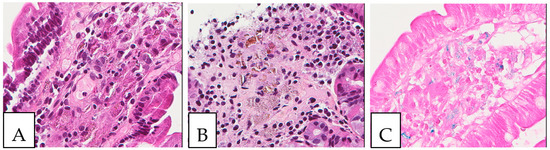

5. Pathologic Features